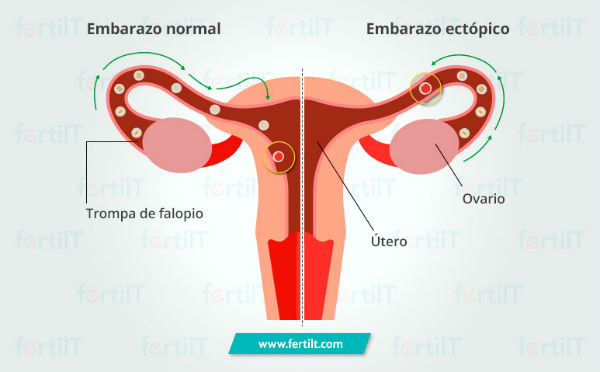

Cuando el óvulo por algún motivo se queda atorado sin alcanzar el útero y es fecundado en el lugar, se produce lo que se conoce como un embarazo ectópico. Este se puede generar en las trompas de falopio, en el cuello uterino o en los ovarios. Es decir, fuera del útero, que es el único lugar en el cual un embarazo podría desarrollar todo su ciclo de forma exitosa.